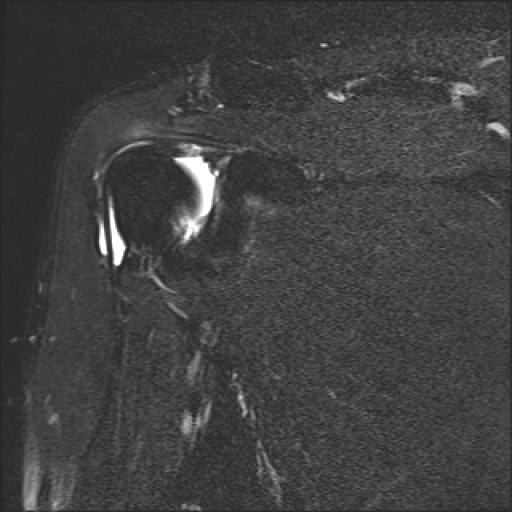

約1年半前のMRI画像ですが、

肩関節内にかなりの水が溜まっていたようです。

右記画像。